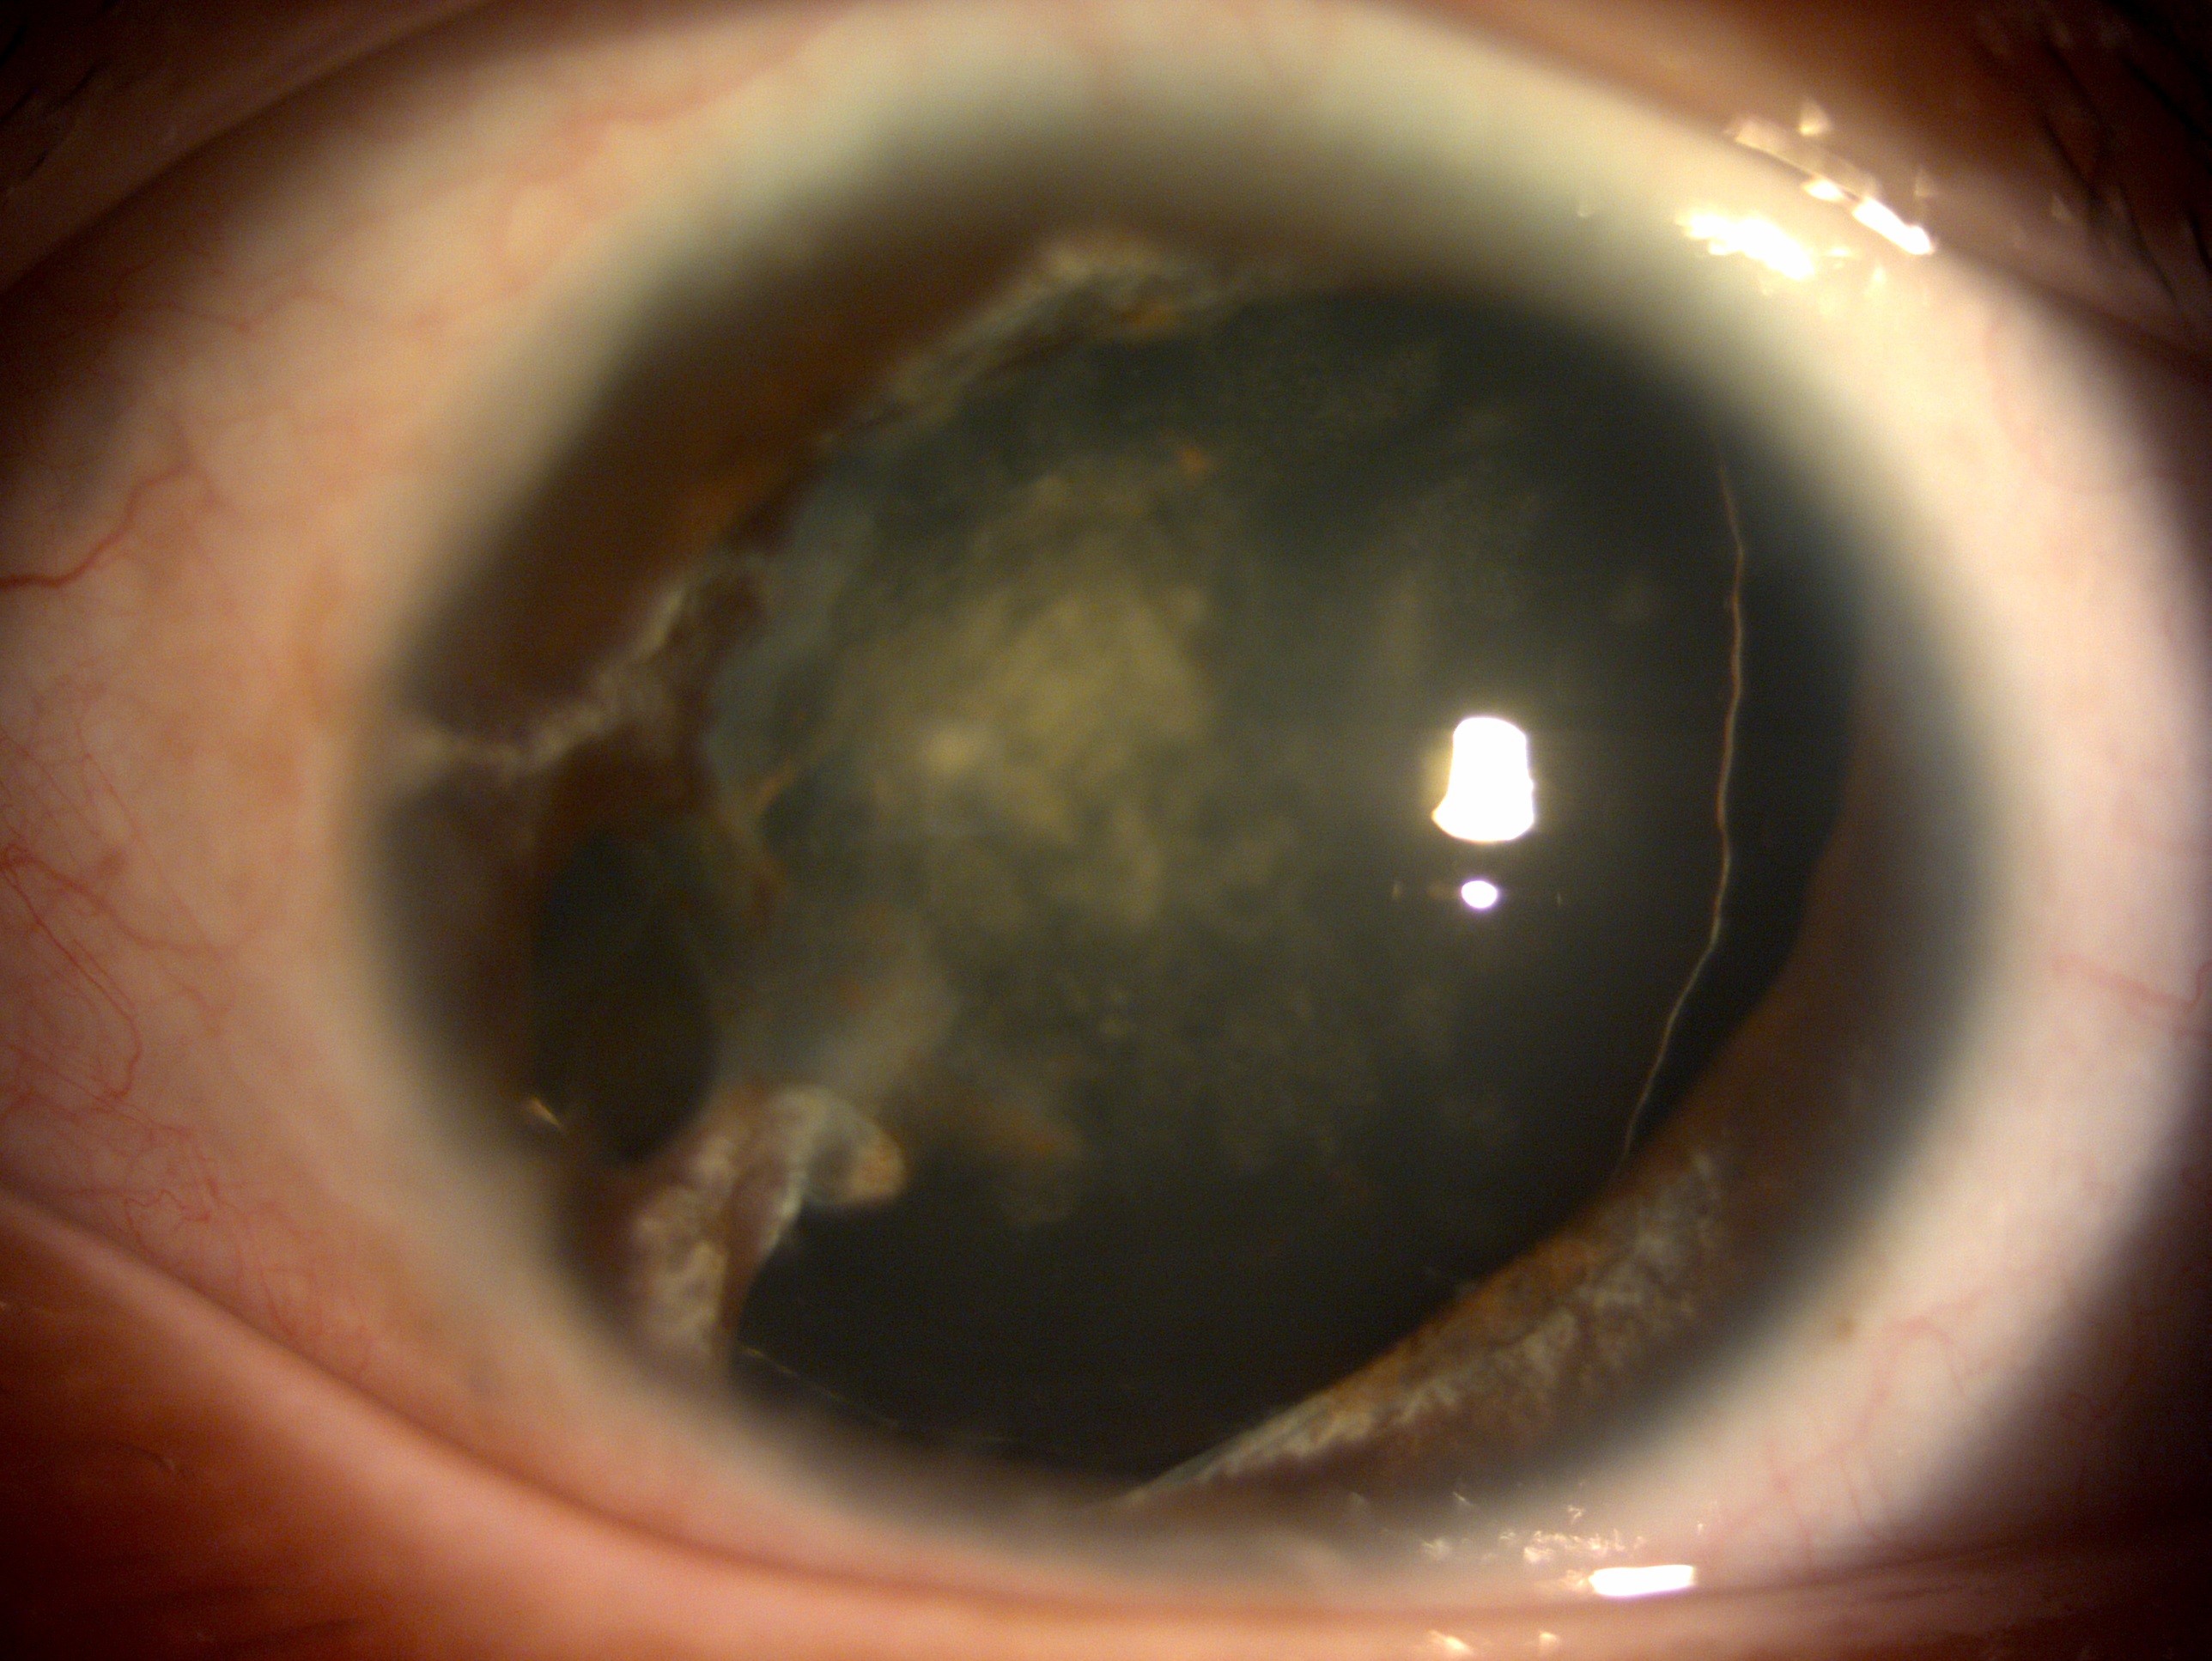

圖1為水晶體脫位病人術前照片

圖2為進行囊袋修復、白內障手術及置入多焦點人工水晶體之術後照片